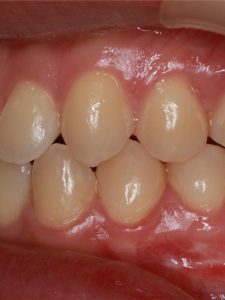

Jaw Repositioning (Orthognathic) Surgery

Before and After Images